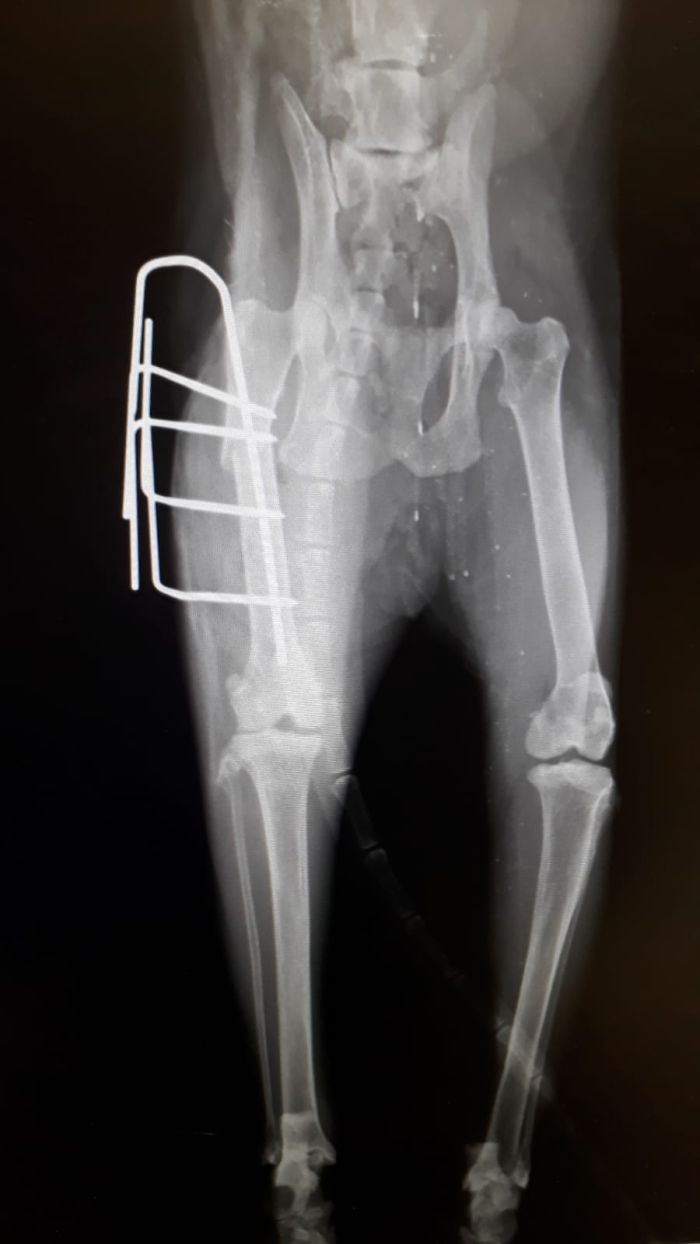

Plattenosteosynthese

Hierbei wird eine Metallplatte  als "Kraft (über-) träger zwischen den Knochenbruchstellen verwendet. Es gibt es eine Vielzahl an Platten ( Abstützplatte, Neutralisationsplatte, Kompressionsplatte, etc.) mit diversen Größen und Längen. Die Metallplatte wird mit speziellen Schrauben (z.B.: Corticalisschrauben / Spongiosaschrauben / ...) am Knochen fixiert.

Fixation durch Markraumnägel / Pins

Zusätzlich zur Plattenosteosynthese werden öfters sogenannte Pins oder Markraumnägel verwendet, um einen Bruch in der Längsachse zu stellen.